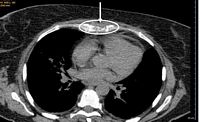

Twelve months later, sternal  osteolysis (Figure 1) and a 6th left rib fracture were identified. Haematological investigation revealed anaemia (8 g/dL), WBC of 20 x 109/L with neutrophilia and Plt of 150 x 109/L. Rib and sternal biopsies (Figures 2 and 3) revealed the diagnosis of acute megakaryoblastic leukemia (AML7). Cells expressed: CD34, CD31, EMA (epithelial membrane antigen), lysozym, factor VIII and MPO. They were negative for: CD3, CD5, CD20, CD73a, CD56, CD68, and CD15AB antigens. Karyotype remained normal.

Figure 1. Scanner view of lytic lesions on the sternum